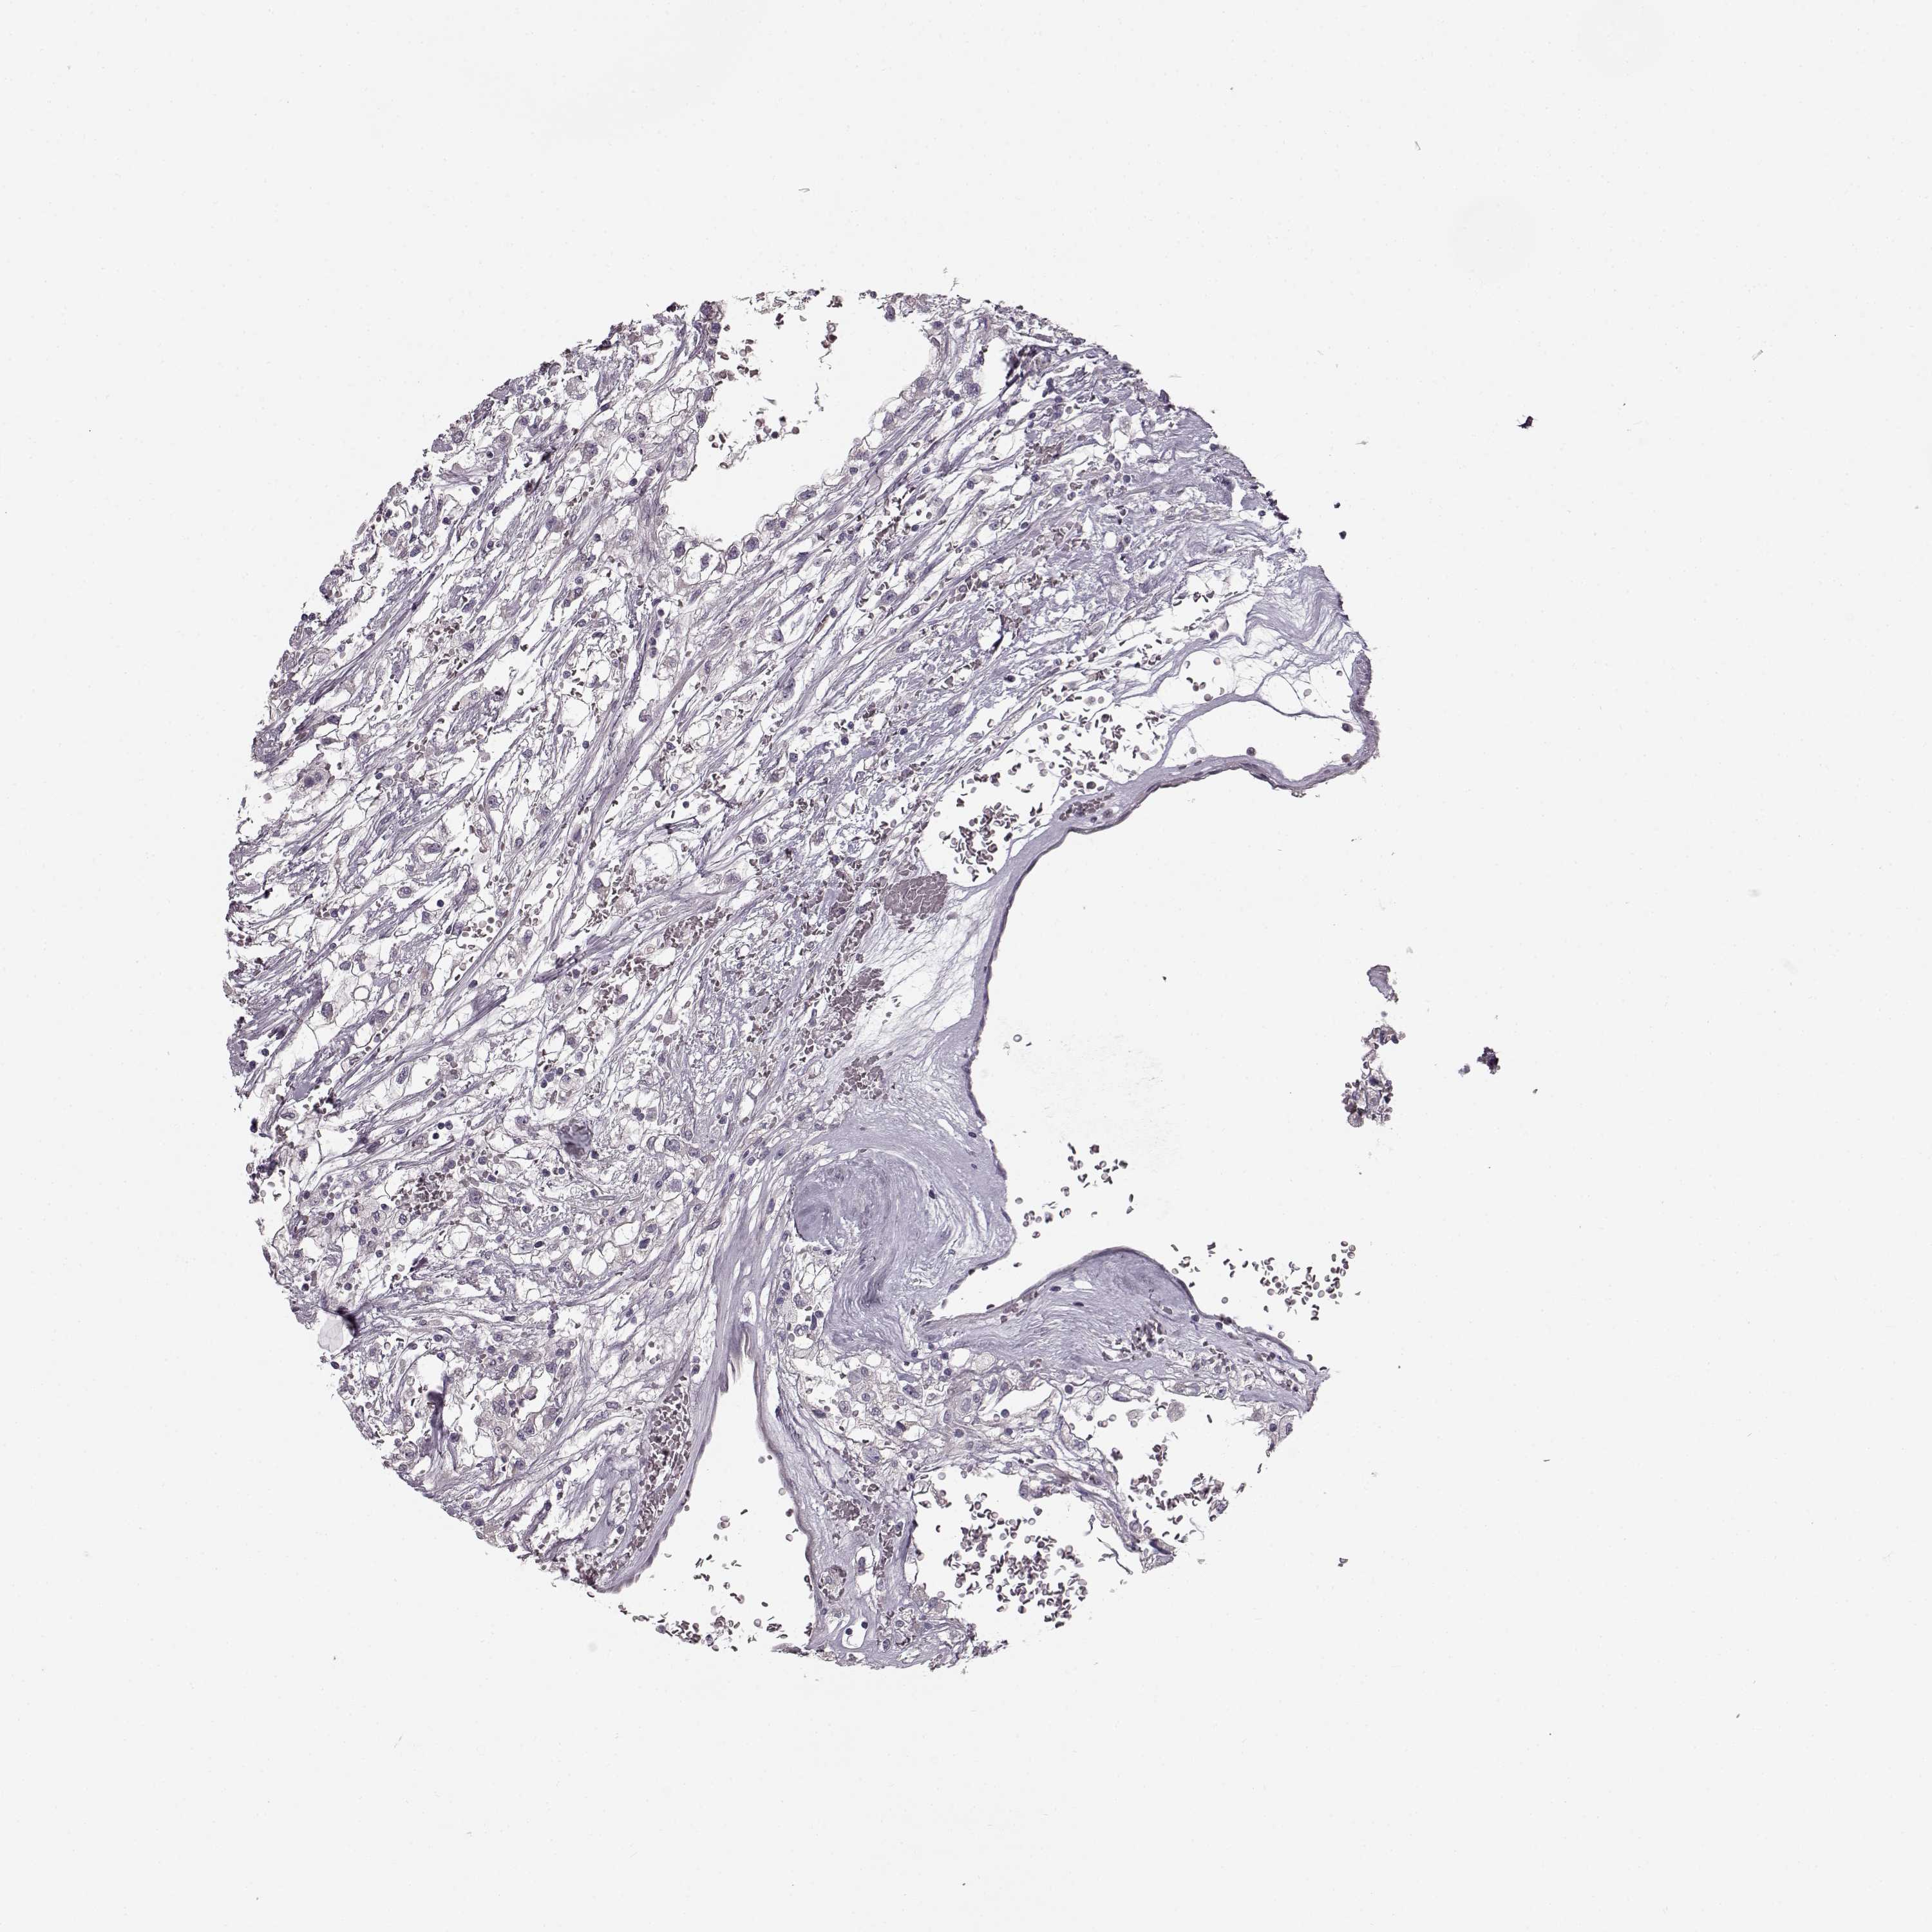

Kidney renal papillary cell carcinoma

KIDNEY RENAL CLEAR CELL CARCINOMA (VALIDATION) - Interactive survival scatter ploti

The Survival Scatter plot shows the clinical status (i.e. dead or alive) for all individuals in the patient cohort, based on the same data that underlies the corresponding Kaplan-Meier plots. Patients that are alive at last time for follow-up are shown in blue and patients who have died during the study are shown in red.

The x-axis shows the expression levels (FPKM) of the investigated gene in the tumor tissue at the time of diagnosis. The y-axis shows the follow-up time after diagnosis (years). Both axes are complimented with kernel density curves demonstrating the data density over the axes. The top density plot shows the expression levels (FPKM) distribution among dead (red) and alive patients (blue). The right density plot shows the data density of the survived years of dead patients with high and low expression levels respectively, stratified using the cutoff indicated by the vertical dashed line through the Survival Scatter plot. This cutoff is automatically defined based on the FPKM cutoff that minimizes the p-score. The cutoff can be changed by dragging the vertical line or by entering a cutoff value in the square labeled "Current cut-off".

Under the Survival Scatter plot the p-score landscape (black curve; left axis) is shown together with dead median separation (red curve; right axis). Dead median separation is the difference in median mRNA expression between patients who have died with high and low expression, respectively. It is calculated as follows: median FPKM expression of dead patients with high expression - median FPKM expression of dead patients with low expression. This is intended to aid the user in visually exploring custom cutoffs and the associated p-scores and dead median separation.

Individual patient data is displayed and can be filtered by clicking on one or more of the category buttons on the top of the page. Categories describing expression level and patient information include: high, low, alive, dead, female, male and tumor stages. The scale of the x-axis can be toggled between linear and log-scale by clicking on the "x log" button. Mouse-over function shows TCGA ID, patient information and mRNA expression (FPKM) for each patient.

& Survival analysisi

Kaplan-Meier plots summarize results from analysis of correlation between mRNA expression level and patient survival. Patients were divided based on level of expression into one of the two groups "low" (under cut off) or "high" (over cut off). X-axis shows time for survival (years) and y-axis shows the probability of survival, where 1.0 corresponds to 100 percent.

MAP6D1 is not prognostic in Kidney Renal Clear Cell Carcinoma (validation)